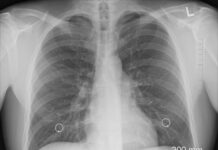

Sve o tuberkulozi koja se pojavila u Novom Pazaru među decom: Odakle bolest i...

U Novom Pazaru tuberkuloza je otkrivena kod devetoro dece, a u toku su...

NOVI PAZAR: Tuberkuloza otkrivena još kod dva učenika i jednog deteta predškolskog uzrasta

Specijalista epidemiologije Safet Ganić rekao je danas da je kod još dva učenika...